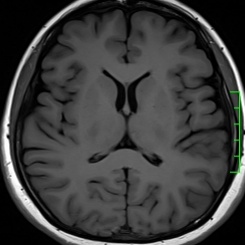

磁共振——锁定“水”的科技

磁共振(MRI)与普通X线、CT不同,不依赖于X线成像,而是氢原子核,也可以理解为水。以前称为核磁共振,是因为MRI的原理是用较大的磁场,使人体内原本随意排列的氢原子核磁场的磁力线方向统一,再突然把磁场的作用去掉,监测其中信号的变化。MRI成像依靠不同组织含氢核数目不同,或者可以近似理解为不同组织含水量不同,形成图像差异,来区别组织。所以MRI对中枢神经系统和软组织有着良好的分辨能力,适用于软组织、神经系统疾病、内脏器官,并且多序列及多参数成像、功能成像。不过,MRI检查时间较长,价格较贵,预约时间较长。

磁共振平扫图像